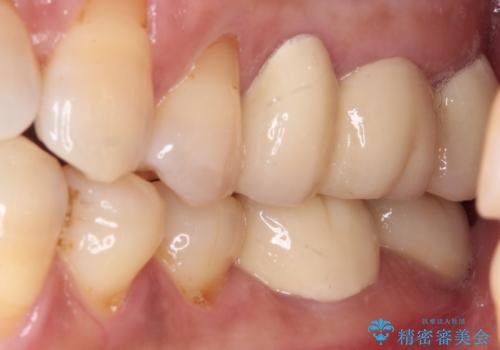

骨よりも深く進行したむし歯 即時荷重インプラントでの短期間治療

- 左下奥のクラウンに違和感を感じるとのことで来院された患者様です。

最後方歯は歯槽骨よりも深い部分にまでむし歯が及んでおり、患者様と相談の上、インプラントによる補綴治療を行うこととしました。

根尖部の病変が小さいことから抜歯即時埋入が選択されるところですが、抜歯窩洞が大きくなることと、窩洞直下に神経や血管が走行していることから、抜歯してから2,3ヶ月待機してから埋入することとしました。

手前の歯は、適合の悪いクラウンを最後方歯と同時にオールセラミッククラウンにて補綴治療を行うこととしました。

骨の高さが不十分であったため、インプラント強度を維持しながらも高さの小さいインプランを使用しました。